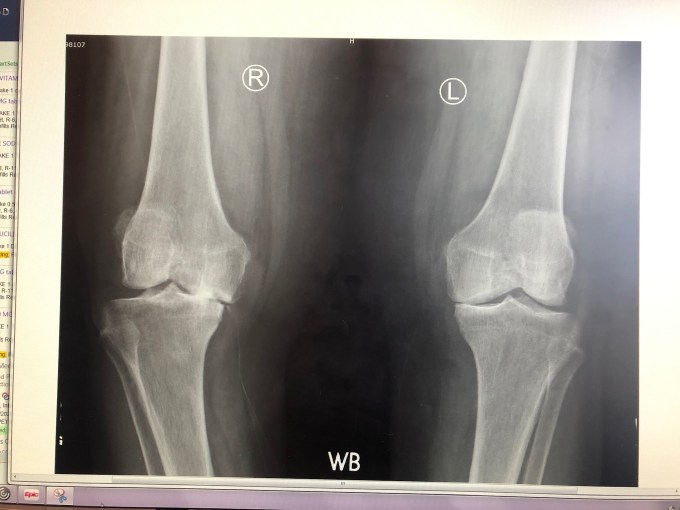

Within 30-minutes, Dr. P, his student, PA, and I were gathered around his monitor, and he said, “This is bad, really bad.” I’m no radiologist, but having seen my own healthy knee x-rays, knew this looked pretty dire. He then said to his collective audience, “It’s memory test time!” and went through a series of clicks to get back to mom’s Feb 2019 knee x-rays. I gasped out loud while uttering, “Oh my God!!” Dr. P said she needs a new knee. I looked at him and said, “We’re not going there. There’s no way she could do the rehab.’ He understood and agreed.

He next pointed out fracture lines along the top of the fibula. He couldn’t hypothesize how this could have happened. We don’t get to know.